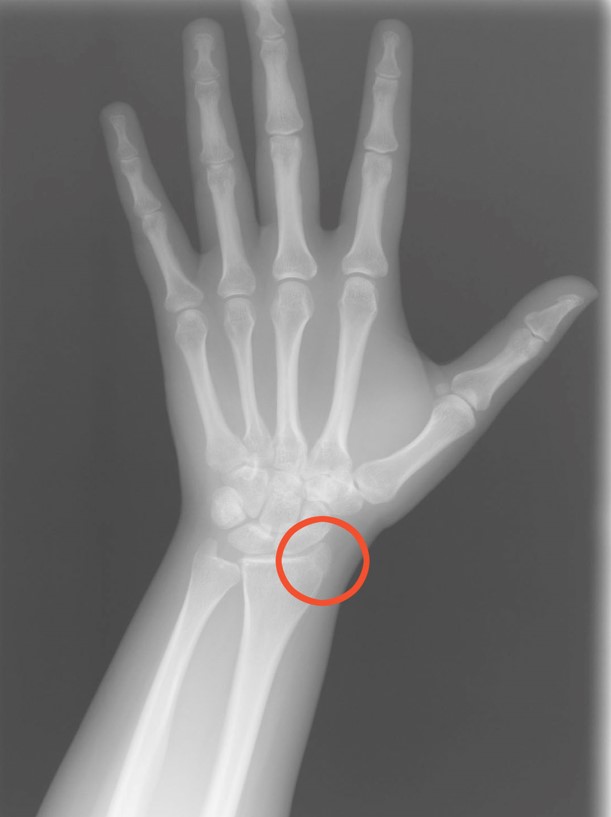

Nova har numera ett paket gips på sin arm, lindat i röd fin bandage. Allt började med att hon lekte i lekparken, men när hon hade klättrat upp och ställt sig på en parkbänk så tappade hon balansen och föll ner. Det gjorde självklart ont och hon blev ledsen, jag kollade så att hon kunde röra armen och om hon hade känseln kvar. Det verkade inte så farligt till en början, men efter att några klasskamrater råkade springa in i hennes onda hand några dagar senare så fick hon ännu ondare, så då åkte vi in till sjukhuset för att kolla upp så inget var brutet. Efter många timmars väntan så fick Nova tillslut röntga handleden där hon hade mest ont, och där kunde man se en början på en liten spricka i ett av benen.

Sprickan kommer att läka fint av sig själv, men för att skydda handleden lite extra så fick hon en liten gipsskena som skulle se till att handen inte böjer sig i onaturligt mycket och förvärrar sprickan. Nova tyckte det var superskoj, även om hon bara ska ha gipset någon vecka eller så. Efter en vecka ska vi tillbaka och röntga handleden igen och se om de kan ta bort gipset, men Nova tycker ju det är så coolt med gipsad arm så vi får se vad läkaren säger då. Hon behöver egentligen inte ha det så det var ingen fara inför skolavslutningen som väntar, tills dess skulle de definitivt ta bort det berättade läkaren vi träffade. To be continued…